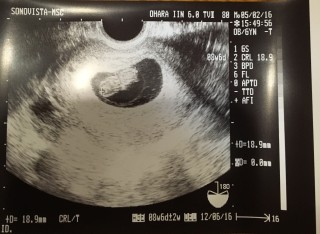

念願の3人目。 2週間ぶりの検診でドラえもんに変身してました!かわいい… 3人目でもやっぱり検診日は待ち遠しくてウズウズしちゃいますね! ベビたんの大きさは1.91センチでした!

5w目から3週間後の待ちに待った検診でした。 心拍の確認も出来、出産予定日も決まり、無事母子手帳もゲット出来ました。 きのこみたいな形してて面白い。笑